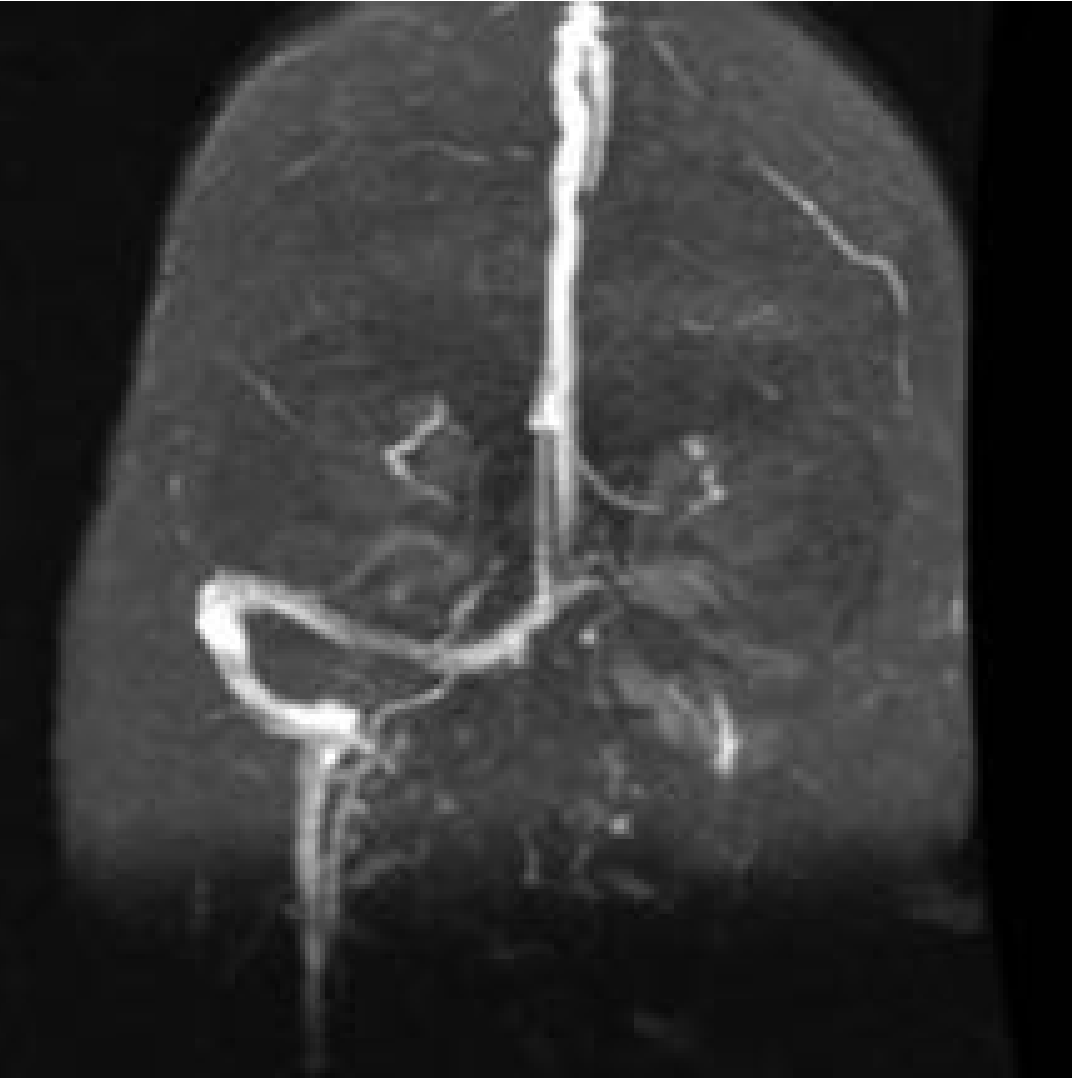

2. MRI + MR Venography (Gold Standard):

• MR Venography: Shows absence of flow / filling defect in sigmoid/transverse sinus (see below)

MR Venogram showing occlusion of left transverse-sigmoid sinus system with absent flow on the affected side

Fig: Magnetic resonance venogram shows occlusion of left transverse-sigmoid sinus system. — Cummings Otolaryngology, p. 2722